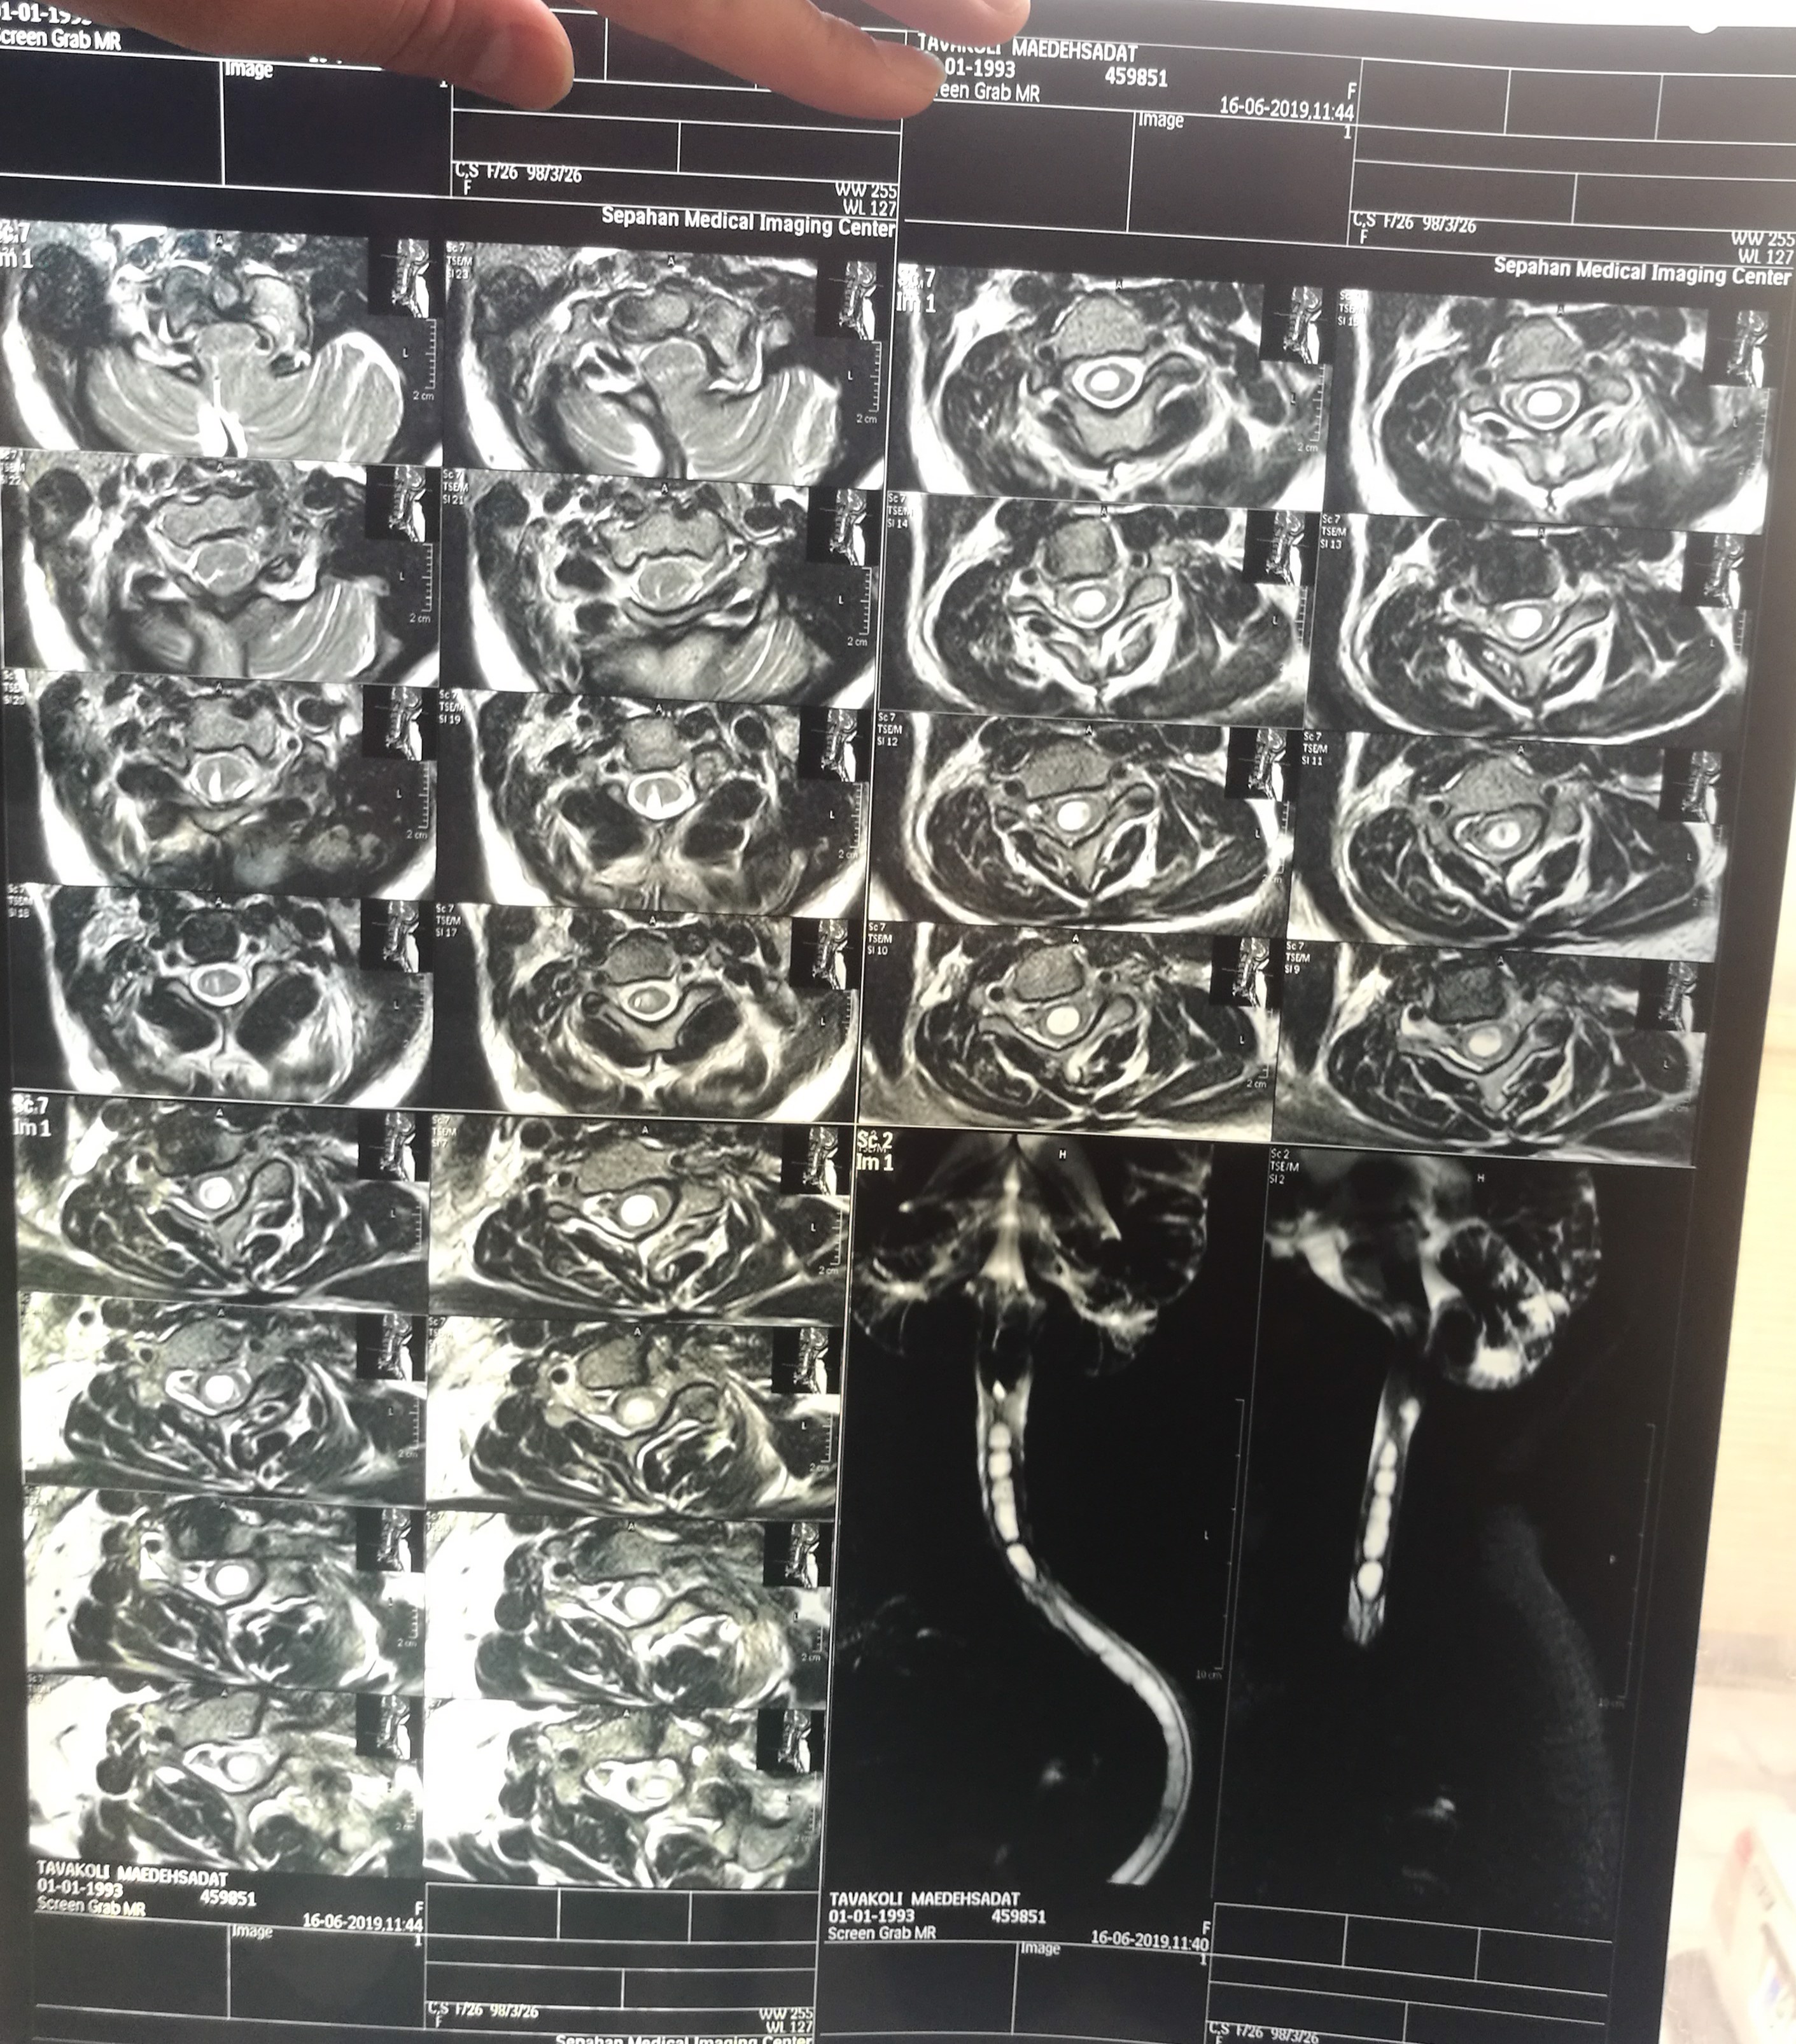

One year ago, I passed out and went to a doctor who said I had a tumor. A few weeks later, I felt a headache and pain in my hands, so I went to a new doctor and he laughed and said I didn't have a tumor and surgery wouldn't help. I didn't accept that and went to another doctor who said I should have surgery because if I didn't, I would die in a few weeks. Surgery would ensure a 20% chance to survive. When I went back home, I stayed in my room the whole night and thought about the people I loved. If these were going to be my last days, thinking of them made me decide to fight with all my whole power and choose to live. I knew how to handle the pain from hard times in my childhood.

I found another doctor who was the best in my country. He said the same words and introduced me to another doctor in my city. I went to that doctor immediately and found he was my reason for hope. God gave me a way to find the best person for this surgery; he said their words but also said: "you can fight and pass these hard times with this power." Everyone in the hospital told him not to perform surgery on me, but he and his team gave me hope and constantly asked me to stay strong. "We need your power," I promised them that I would use all my power. My surgery was about 5 hours. I remember the moments before the surgery someone came to my doctor and said don't do this, she won't stay alive....but we didn't care. I recovered in 45 min, no one believed this and they brought me to the ICU where I had to use a ventilator to breathe and I couldn't talk or eat. I just spoke with my eyes and hands. The first day my doctor came to me and looked at my eyes and held my hands and said " thanks for fighting and only you could do this. Your surgery was so hard and dangerous but I did it in the best way." I could see his worry about me as though I was part of his family. He called ICU every couple hours to check up on me.